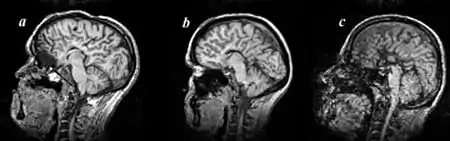

MRI images of three patients in the sagittal plane. A and B: Complete agenesis of the corpus callosum. C: Complete agenesis of both the corpus callosum and the anterior commissure.